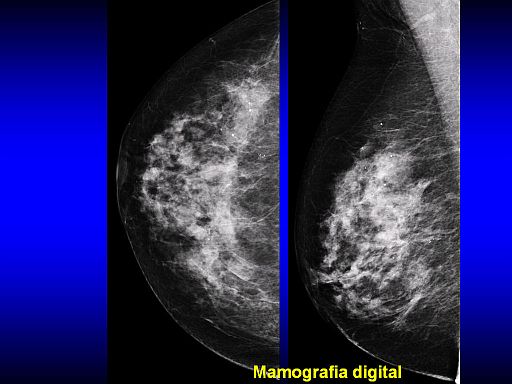

Entra em operação o primeiro equipamento de tomossíntese do país. Recentemente apresentado na Jornada Paulista de Radiologia, a mamografia em 3D elimina a superposição de tecidos, melhora a visualização dos contornos das lesões e aumenta entre 10% e 15% a detecção da doença, de acordo com estudos iniciais.

Na opinião de Aron Belfer, em termos de tecnologia, a mamografia digital 2D é um avanço importante em relação à mamografia analógica, convencional. Já a tomossíntese, de acordo com estudos recentes, surge como uma tecnologia capaz de detectar lesões que antes passariam despercebidas na mamografia digital 2D. “A detecção de tumores menores permite recorrer a cirurgias menos mutilantes, resulta em menor custo global do tratamento, maior sobrevida e melhor qualidade de vida das pacientes”.